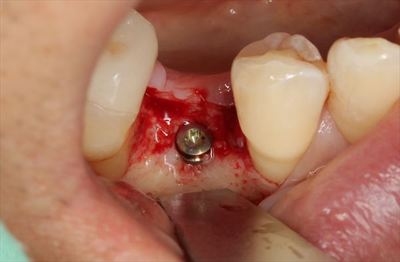

φ3.3㎜のインプラントを埋入しますので、φ2.8㎜のドリルが最終ドリルです。

深度ゲージで確認を行います。